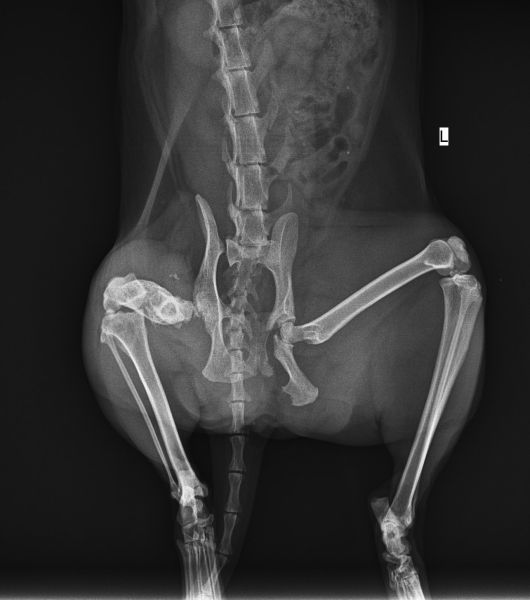

One of my cats (female, at least 9 years old) has apparently been hit by a car earlier today. I took her to a vet which took 2 X-rays.

There is an acetabular fracture and a sacroiliac separation.

It may be required to operate only on the acetabular fracture, or it may be needed to fixate the sacroiliac separation.

One of the traumas is on the cup of the hip joint (the "acetabulum", right?). Even if we can fix it, the risk of developing coxarthrosis ("hip osteoarthritis", right?) after some time, which will be painful and will require further surgery, is high.

He suggested we remove that joint - resection of femoral head. After the joint is removed, it will be replaced with a "fake" joint that the cat already has on the other side with the previously-broken leg.

The other fracture the hip is separated from the spine, but it doesn't bear weight there, so it might be treated conservatively (without surgery).